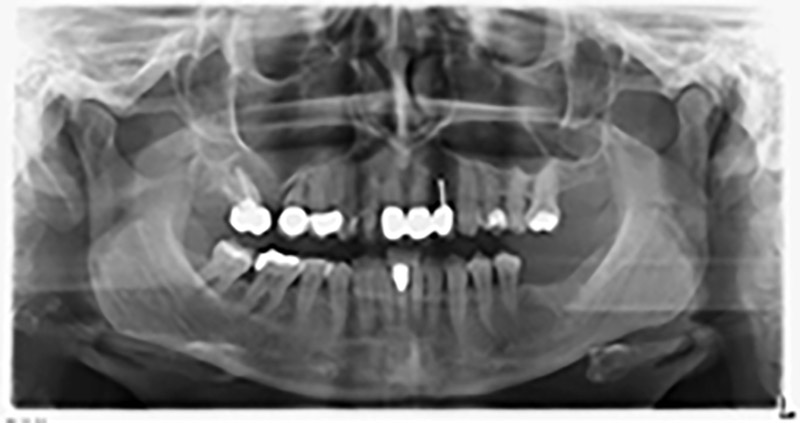

La paziente, 59 anni, presenta un caso di parodontite avanzata e descrive una sensazione di fastidio e scarsa sensibilità gustativa dal primo quadrante in direzione distale. L'esame clinico rivela tasche parodontali generalmente diffuse e un'atrofia ossea molto avanzata nelle regioni 16 e 14. L'esito è confermato dalla radiologia (fig. 1). Non è possibile salvare i denti 16 e 14.

Immagine 1: ortopantomografia con artrofia ossea nella regione 16–14. *